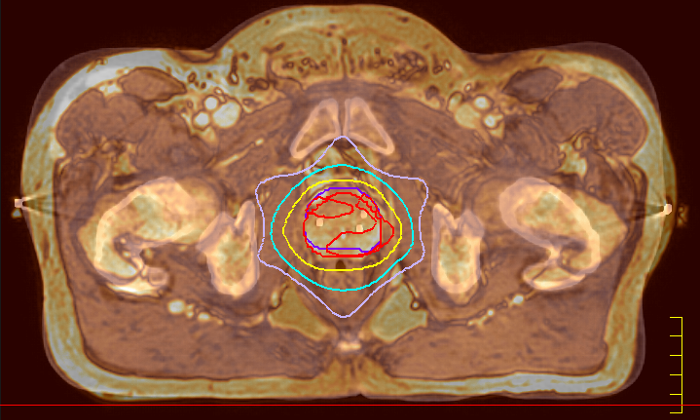

With its exceptional soft-tissue visualization capabilities and wide range of image contrasts, MRI has become a powerful tool to help more precisely define tumor boundaries. This is particularly important as it has been established that there is a high degree of uncertainty in target volume delineation, and it is even reported to represent the largest uncertainty in the entire radiotherapy process for most tumor sites**. Better visualization of the target area and nearby organs-at-risk is a key factor in enhancing target volume delineation. MRI’s expanding role also can be attributed to its functional imaging capabilities, which can inform both target characterization and treatment response.

Our innovative MRCAT (MR for Calculating ATtenuation) clinical applications lets you plan radiation therapy using MRI as primary imaging modality. Within just one, fast MR exam, MRCAT provides both excellent soft-tissue contrast for target and OAR delineation and CT-like density information for dose calculations.

This not only extends the benefits of MRI’s excellent soft-tissue contrast to radiotherapy planning, but it also eliminates arduous, error-prone CT-MRI registration from the process, reducing uncertainties and complexity.

Ingenia MR-RT is a dedicated MR simulation platform that provides high quality, high contrast MR images acquired with the patient in treatment position. Designed for the needs of radiation oncology, this comprehensive solution provides the tools and software needed for versatile and efficient imaging for radiotherapy planning.